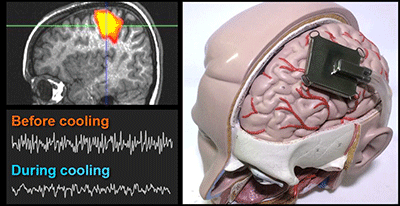

Simulating effects of focal brain cooling against epilepsy

―Towards development of a less-invasive ...